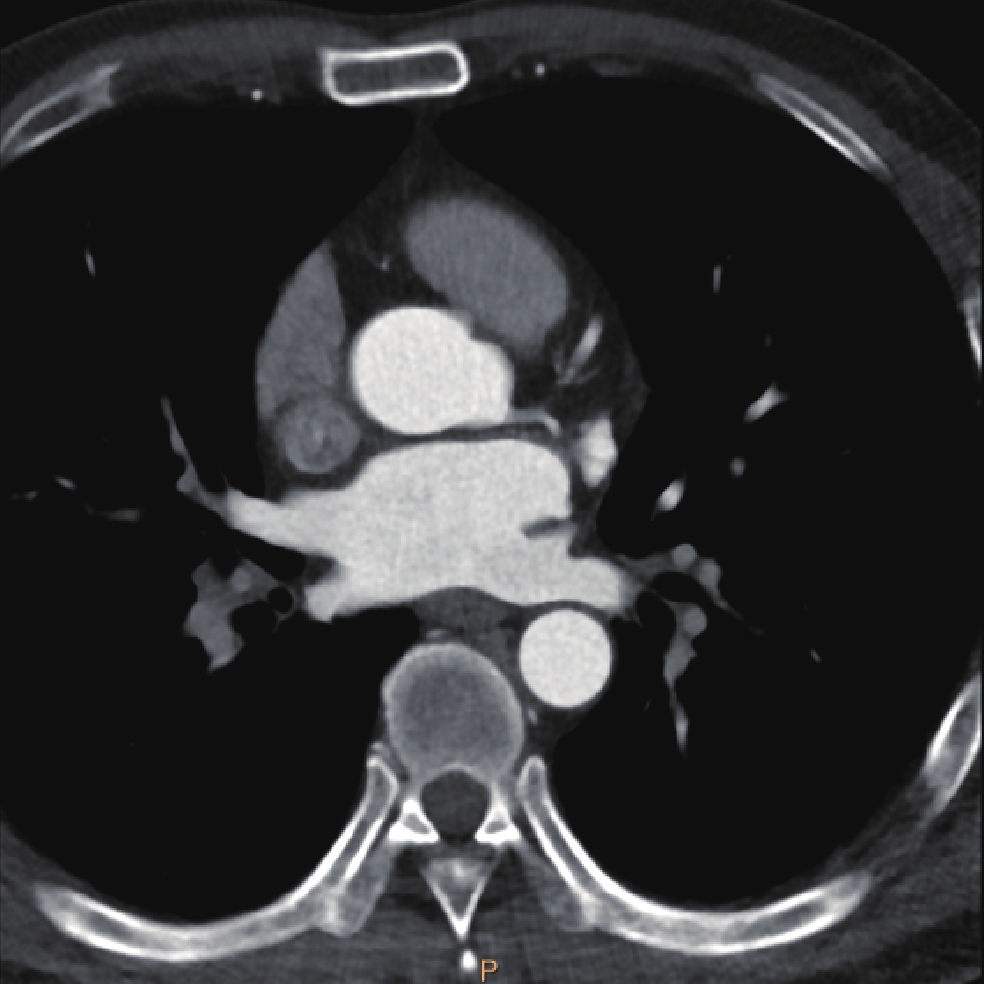

• 摘要: 目的:探讨不同扫描模式对胸主动脉CTA图像质量和辐射剂量的影响。方法:回顾性分析未应用心电门控技术的30例胸主动脉CTA(组1,对照组),使用回顾性心电门控的30例冠脉CTA重建舒张期(组2)和收缩期(组3)时相,30例应用宽曝光脉冲前瞻性心电门控技术(组4)共4组图像的质量和辐射剂量。分别记录、计算4组的图像质量客观指标CT值、噪声、CNR和辐射剂量指标CTDIvol。对图像质量进行四分法主观评价。对主客观指标分别统计分析。结果:客观指标CNR组1与组2、3、4均有差异,组2、3、4间均无差异;主观评分两两比较组2~4显著高于组1,组2~4间无差异。非门控组(组1)、回顾门控组(组2和组3)和前瞻门控组(组4)的CTDIvol分别为13.70(11.87,16.58)、12.62(10.03,15.01)、11.54(8.92,15.56),差异无统计学意义。结论:在胸主动脉CTA中推荐使用窄曝光脉冲的前瞻性心电门控收缩期或舒张期扫描,可显著提高胸主动脉心脏段图像质量并降低辐射剂量。

Abstract: Objective: This study aimed to compare the effects of different scanning modes on image quality and radiation dose in thoracic aortic computed tomography angiography (CTA). Methods: The image quality and radiation dose of 30 cases of thoracic aortic CTA (Group 1, control group), 30 cases of retrospective CTA diastolic phase (Group 2) and systolic phase (Group 3), and 30 cases of wide-exposure pulse prospective electrocardiogram (ECG) (Group 4) were retrospectively analyzed. The CT value, noise, contrast-to-noise ratio (CNR), signal-to-noise ratio (SNR), and radiation dose (volume CT dose index CTDIvol) were recorded and measured. The image quality was evaluated subjectively using the four points method. The subjective and objective indicators were analyzed statistically. Results: No differences were observed in the objective indexes of noise, CNR and SNR among the groups. The subjective score of pairwise comparison of Groups 2~4 was significantly higher than that of Group 1, and no difference was observed among Groups 2~4. The CTDIvol values of the non-gated group (Group 1), retrospective gated groups (Groups 2 and 3), and prospective gated group (Group 4) were 13.70 (11.87,16.58), 12.62 (10.03,15.01), and 11.54 (8.92,15.56), respectively, without a statistically significant difference.